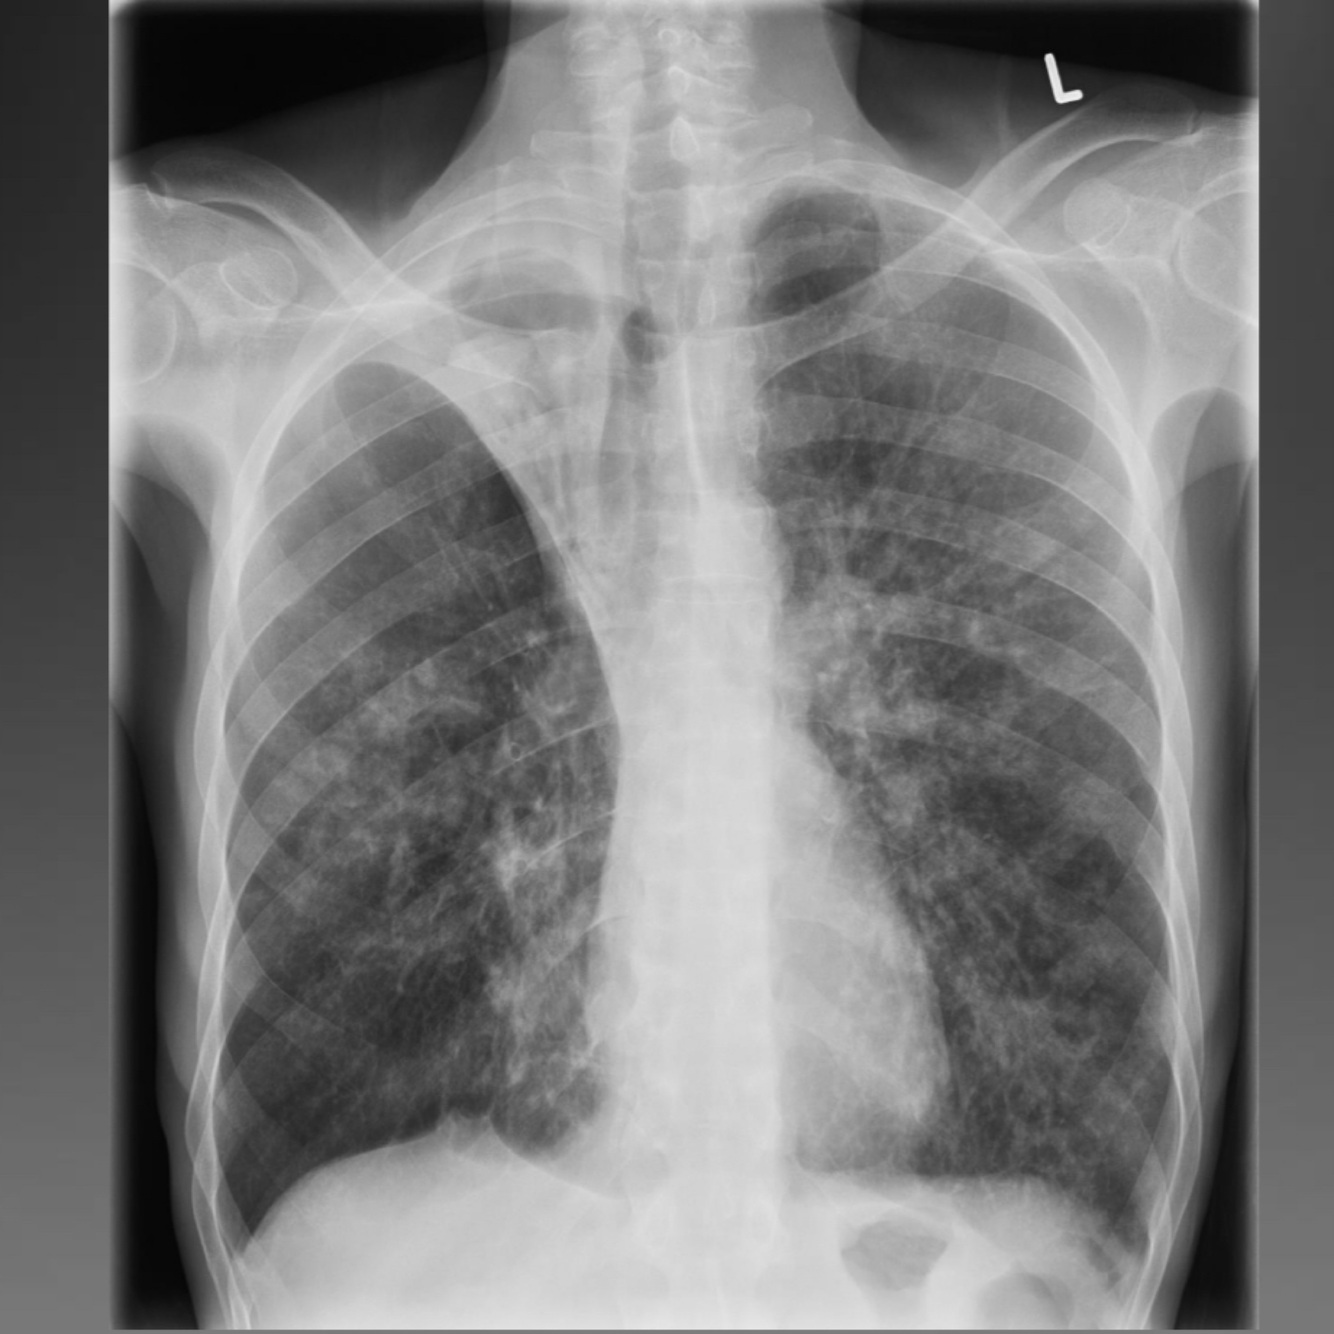

11

Q

Post primary tb

A

Reactivation of latent infection or 2nd infection

SS: typical LOW, LOA, NS, fever, haemoptysis

Cavitation common, often apical and posterior segments

of lung, miliary spread, airway stenosis, SPN (occasionally)

Can be progressive

12

Post primary cavitation